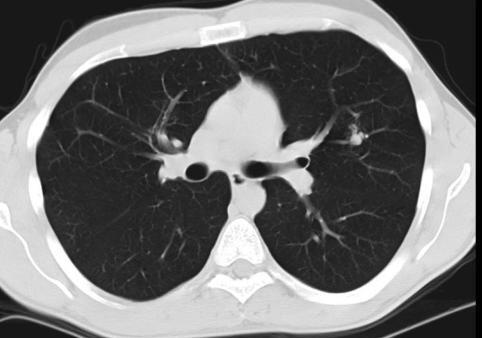

COVID-19 CT Scan

Detecting COVID-19 from Chest CT-Scan

Our software utilises Machine learning schemes for the analysis of Chest CT Scans of COVID-19 patients and is capable of identifying the presence of infection with an average accuracy of 95.37%, with 95.99% sensitivity and 94.76% specificity.